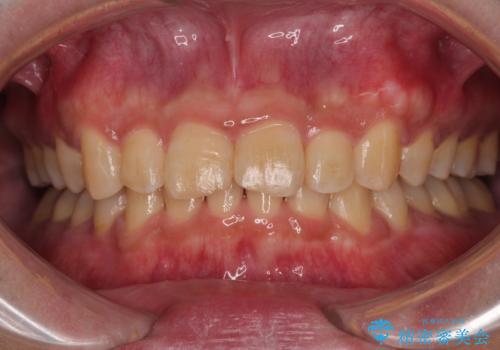

上顎歯列を遠心移動させたことで、前歯の叢生が解消されても前歯が前突することなく、左右ともに理想的な咬み合わせを達成することができました。